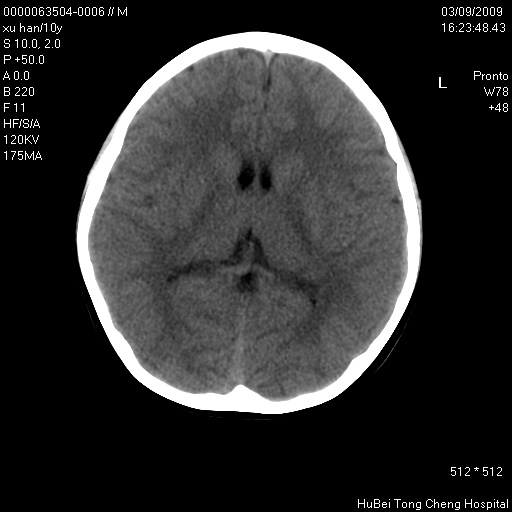

以下是引用道哥在2009-3-9 18:40:00的发言:[br]未见明显异常,必要时mr(dwi)成像。

以下是引用余辉在2009-3-10 11:01:00的发言:[br]考虑双侧海马急性缺氧性损伤